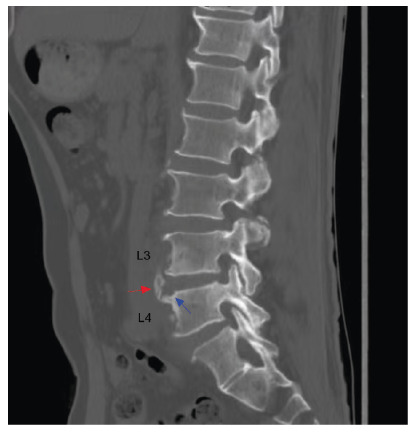

The appearances of a parrot's peak and petal rims in brucellar spondylitis.